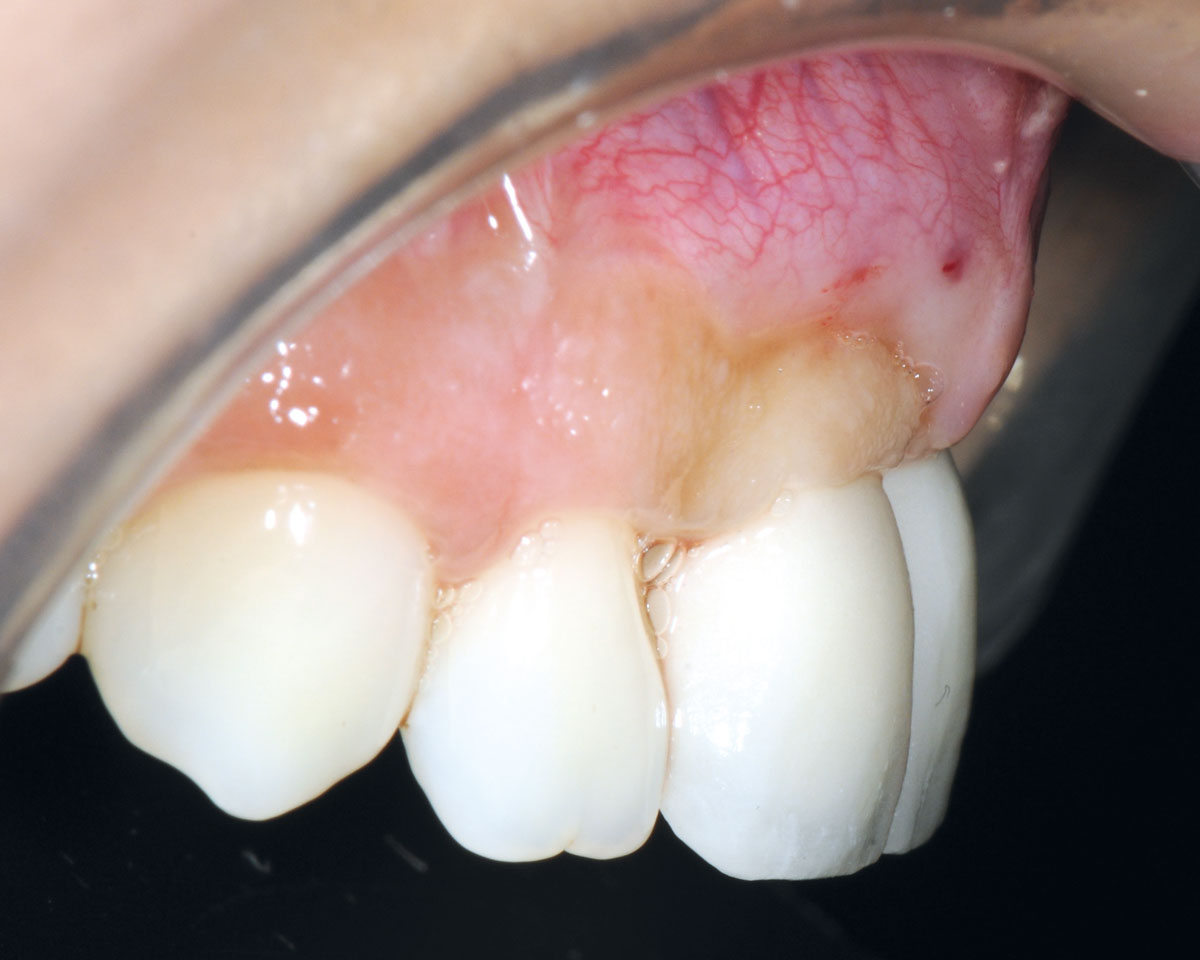

3/26 - Big bone defect visible after opening the flapBone augmentation in aesthetic zone with maxgraft® bonering - Dr. A. Patel